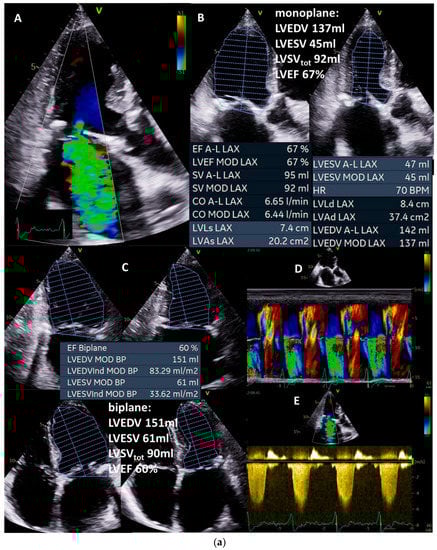

Figure 3.

(a): Illustration of underestimation of LVEDV and LVESV by 2D echocardiography: in (A), the planimetry of LVEDV in the two-chamber view (2-ChV) is shown; in (B), the corresponding LVESV is shown. In (C), the planimetry of LVEDV in the four-chamber view (4-ChV) is shown; in (D), the corresponding LVESV is shown. However, the obvious difference between the longitudinal LV axis in the 4-ChV between diastole and systole indicates the foreshortening of the 4-ChV causing errors of LV volume assessment. LVSV = left ventricular stroke volume, LVSVtot = total LVSV, LVSVeff = effective LVSV, LVEDV = left ventricular end diastolic volume, and LVESV = left ventricular end systolic volume. (b): Measurements of the corresponding LVEDV areas in adjusted sectional planes by postprocessing in a 3D dataset in comparison with the 2D echocardiography presented in (a): in (A), the LVEDV assessment of the adjusted four-chamber view is shown; in (B), the perpendicular lines of the apical planes in the short-axis view of the 3D dataset are shown; in (C), the 3D view of the azimuth plane is shown; in (D), the LVEDV assessment of the adjusted two-chamber view is shown. In (E), a parasternal short-axis view during systole to label the RVOT is shown. In (F), the RVOT-pw-Doppler spectrum is shown. In (G), a parasternal long-axis view during systole to label the LVOT is shown. In (H), the LVOT-pw-Doppler spectrum is shown. Estimation of effective LVSV is performed with pw Doppler echocardiography by determination of forward RVSV. In isolated mitral regurgitation, a countercheck can be performed by assessment of forward LVSV which corresponds to forward RVSV. LVSV = left ventricular stroke volume, RVSV = right ventricular stroke volume, LVSVtot = total LVSV, LVSVeff = effective LVSV, LVEDV = left ventricular end-diastolic volume, RVOT = right ventricular outflow tract, and LVOT = left ventricular outflow tract.